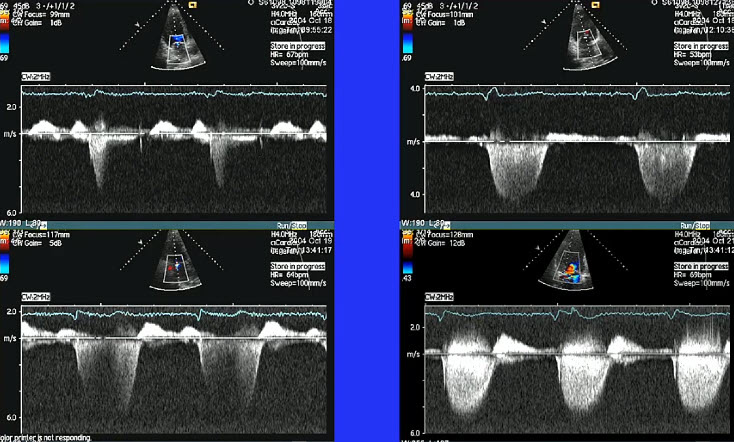

Традиционно диагностика митральной регургитации основывается на визуальной оценке эхокардиограмм врачом-кардиологом. Однако этот процесс субъективен и может зависеть от опыта и квалификации специалиста. Кроме того, анализ большого объема данных может быть трудоемким и занимать много времени. Мы увидели возможность автоматизировать и улучшить этот процесс с помощью искусственного интеллекта.

Нашей целью было создать систему, которая могла бы автоматически анализировать эхокардиографические изображения и выявлять признаки митральной регургитации с высокой точностью и скоростью. Мы верили, что такой инструмент поможет врачам-кардиологам в принятии более обоснованных решений, сократит время диагностики и улучшит результаты лечения пациентов.

- Сбор и разметка данных: Этот этап был одним из самых трудоемких. Нам потребовалось собрать большой объем эхокардиографических изображений, полученных от различных пациентов. Затем каждый снимок был тщательно размечен экспертами-кардиологами, которые указали наличие или отсутствие митральной регургитации, а также выделили ключевые анатомические структуры.

После завершения разработки и тестирования нашей системы мы получили обнадеживающие результаты. На тестовом наборе данных наша модель показала высокую точность в выявлении признаков митральной регургитации. Мы также провели пилотное исследование с участием врачей-кардиологов, которые использовали нашу систему в своей клинической практике. Результаты показали, что использование ИИ-ассистента позволило сократить время диагностики и повысить уверенность в принятых решениях.